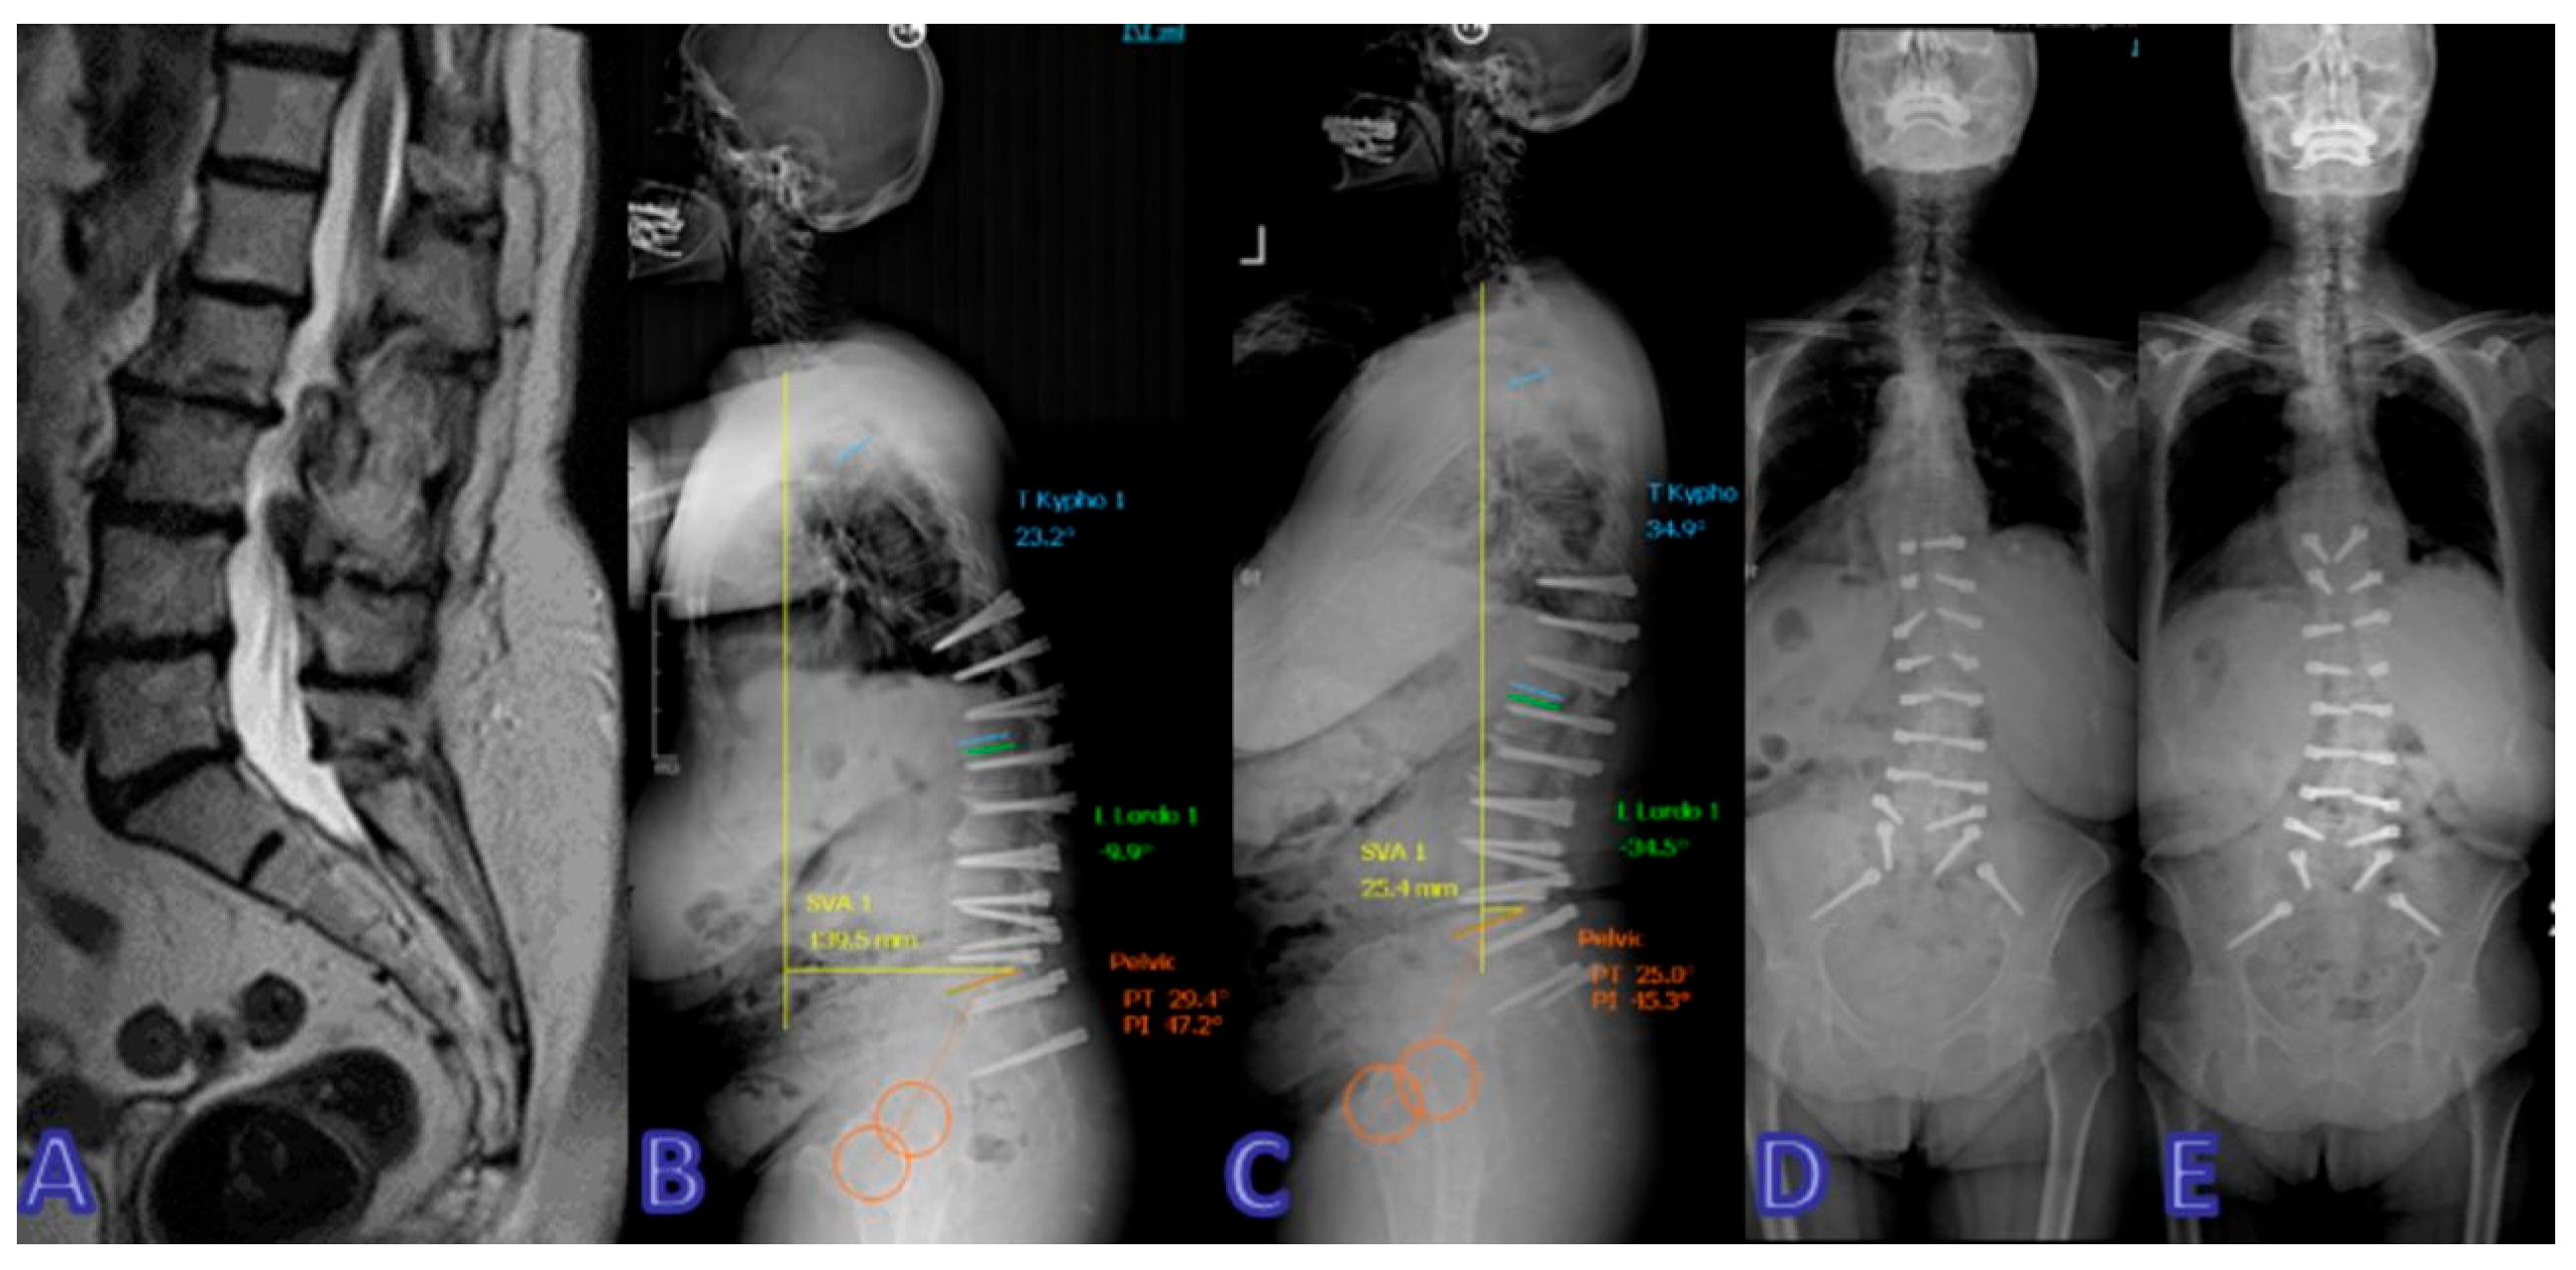

- Ozer, A.F.; Akgun, M.Y.; Ucar, E.A.; Hekimoglu, M.; Basak, A.T.; Gunerbuyuk, C.; Toklu, S.; Oktenoglu, T.; Sasani, M.; Akgul, T.; et al. Can Dynamic Spinal Stabilization Be an Alternative to Fusion Surgery in Adult Spinal Deformity Cases? Int. J. Spine Surg. 2024, 18, 152–163. [Google Scholar] [CrossRef] [PubMed]